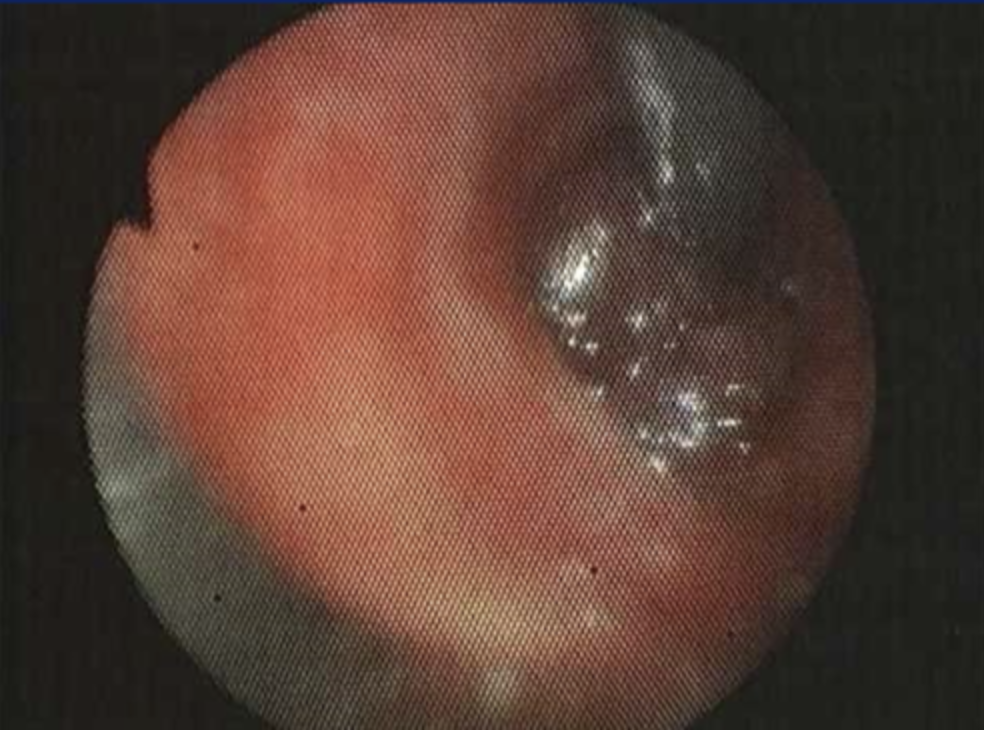

Bronchoscopy of what?

A

Bronchoscopy of Carcinoid Tumor

- looks PINK or PURPLE